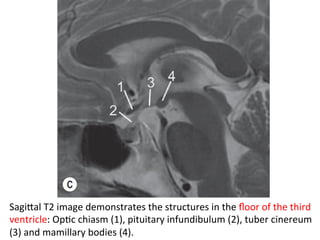

SagiTal	T2	image	demonstrates	the	structures	in	the	floor	of	the	third

ventricle:	OpHc	chiasm	(1),	pituitary	infundibulum	(2),	tuber	cinereum

(3)	and	mamillary	bodies	(4).

-The	hypothalamus	forms	the	floor	of	the	third	ventricle

and	its	side	walls	anteriorly	following	an	oblique	line

inferiorly	from	the	foramen	of	Monro	to	the	midbrain

Aqueduct.